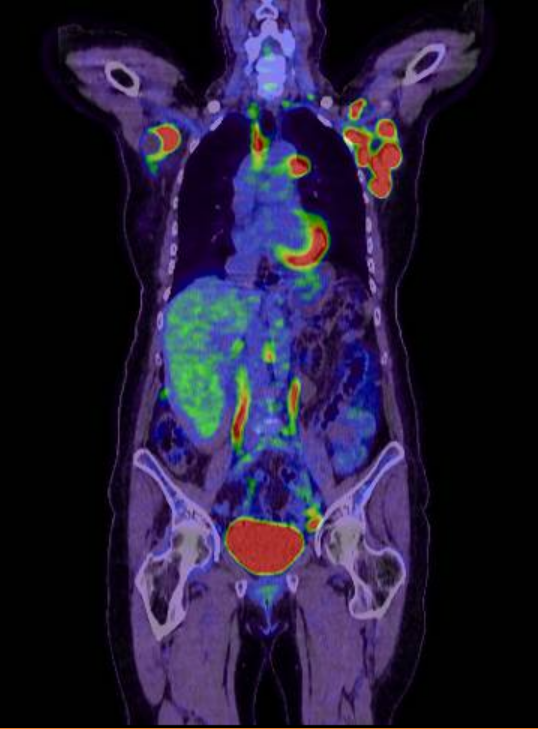

The lymph node biopsy obtained at GenesisCare in Cambridge identified high-grade diffuse large b-cell lymphoma with non-germinal centre. A subsequent PET-CT scan showed nodal disease above and below the diaphragm in keeping with stage 3 lymphoma. The patient had stable bloods with marginally elevated LDH.

(PRE Tx PET CT scan)